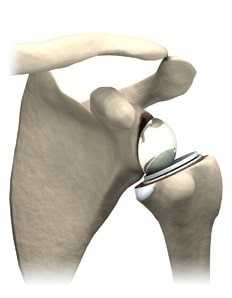

На данный момент времени для эндопротезирования плечевого сустава используются анатомические и реверсивные типы протезов.

Анатомические эндопротезы плечевого сустава

Анатомический эндопротез состоит из плечевого и гленоидного компонента. Гленоидный компонент копирует суставную площадку лопатки, а плечевой компонент заменяет головку и шейку плечевой кости.

Анатомический эндопротез плечевого сустава разработан по подобию и копирует нормальный плечевой сустав. Искусственные суставные поверхности головки и гленоида сохраняют свое естественное соотношение как в нормальном плечевом суставе.

У молодых пациентов с высокой двигательной активностью предпочтительно использовать двухполюсное или тотальное эндопротезирование. При этом виде эндопротезирвоания меняется как плечевой, так и гленоидальный компонент. Тотальный эндопротез позволяет вернуться молодому пациенту к прежней активности, обеспечивает купирование боли, а также характеризуется большим сроком службы.